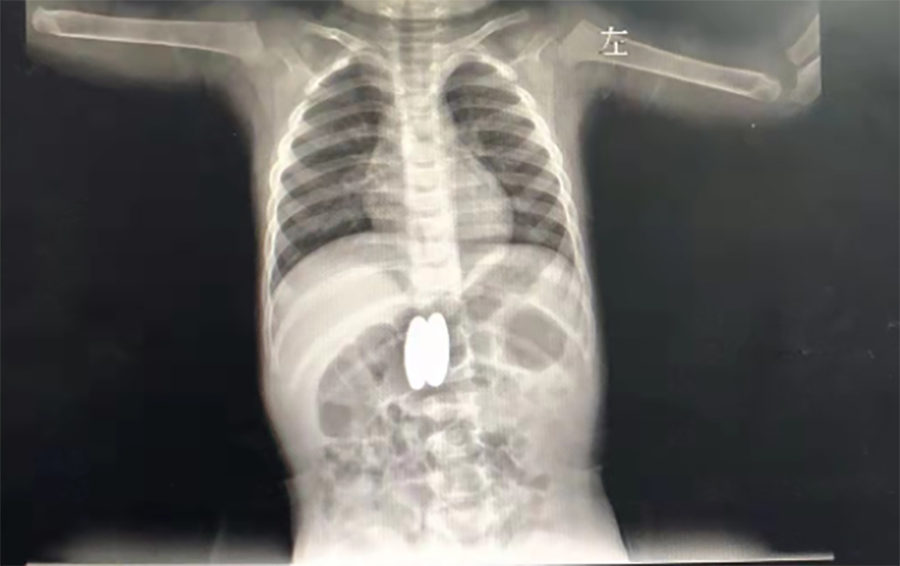

正月初八,2岁的壮壮(化名)感冒加重了,不断咳嗽,家人带他到当地医院就诊。在拍肺CT时,医生发现他的胃、肠里竟然有两个异物,而且两处异物竟吸在一起了。

▲当地医院CT

吞俩磁力球,很可能穿孔

家长回想起春节前大宝的4个磁力球少了2个,怎么找都没找到,看来是被二宝误吞了。当地医生担心壮壮胃肠穿孔,建议他们马上带壮壮到蜜桃视频 就诊。在内镜中心,副主任边鹏经内镜检查,发现壮壮吞下的磁力球直径有2cm,呈椭圆形,分别在胃体后壁、十二指肠球部。考虑到误吞异物时间较长,两球相吸处很可能已经穿孔,内镜中心同外科会诊,迅速研究解决方案。边鹏说,一是手术治疗,但十二指肠周围有胆管、大血管等,周围组织特别敏感,一旦出问题,危险性极大;二是保守治疗,在生命体征平稳的情况下,暂时观察,待胃、肠穿孔形成窦道,就可以不用手术,在内镜下把异物取出来了。经沟通,家长选择保守治疗,择日再来取出异物。